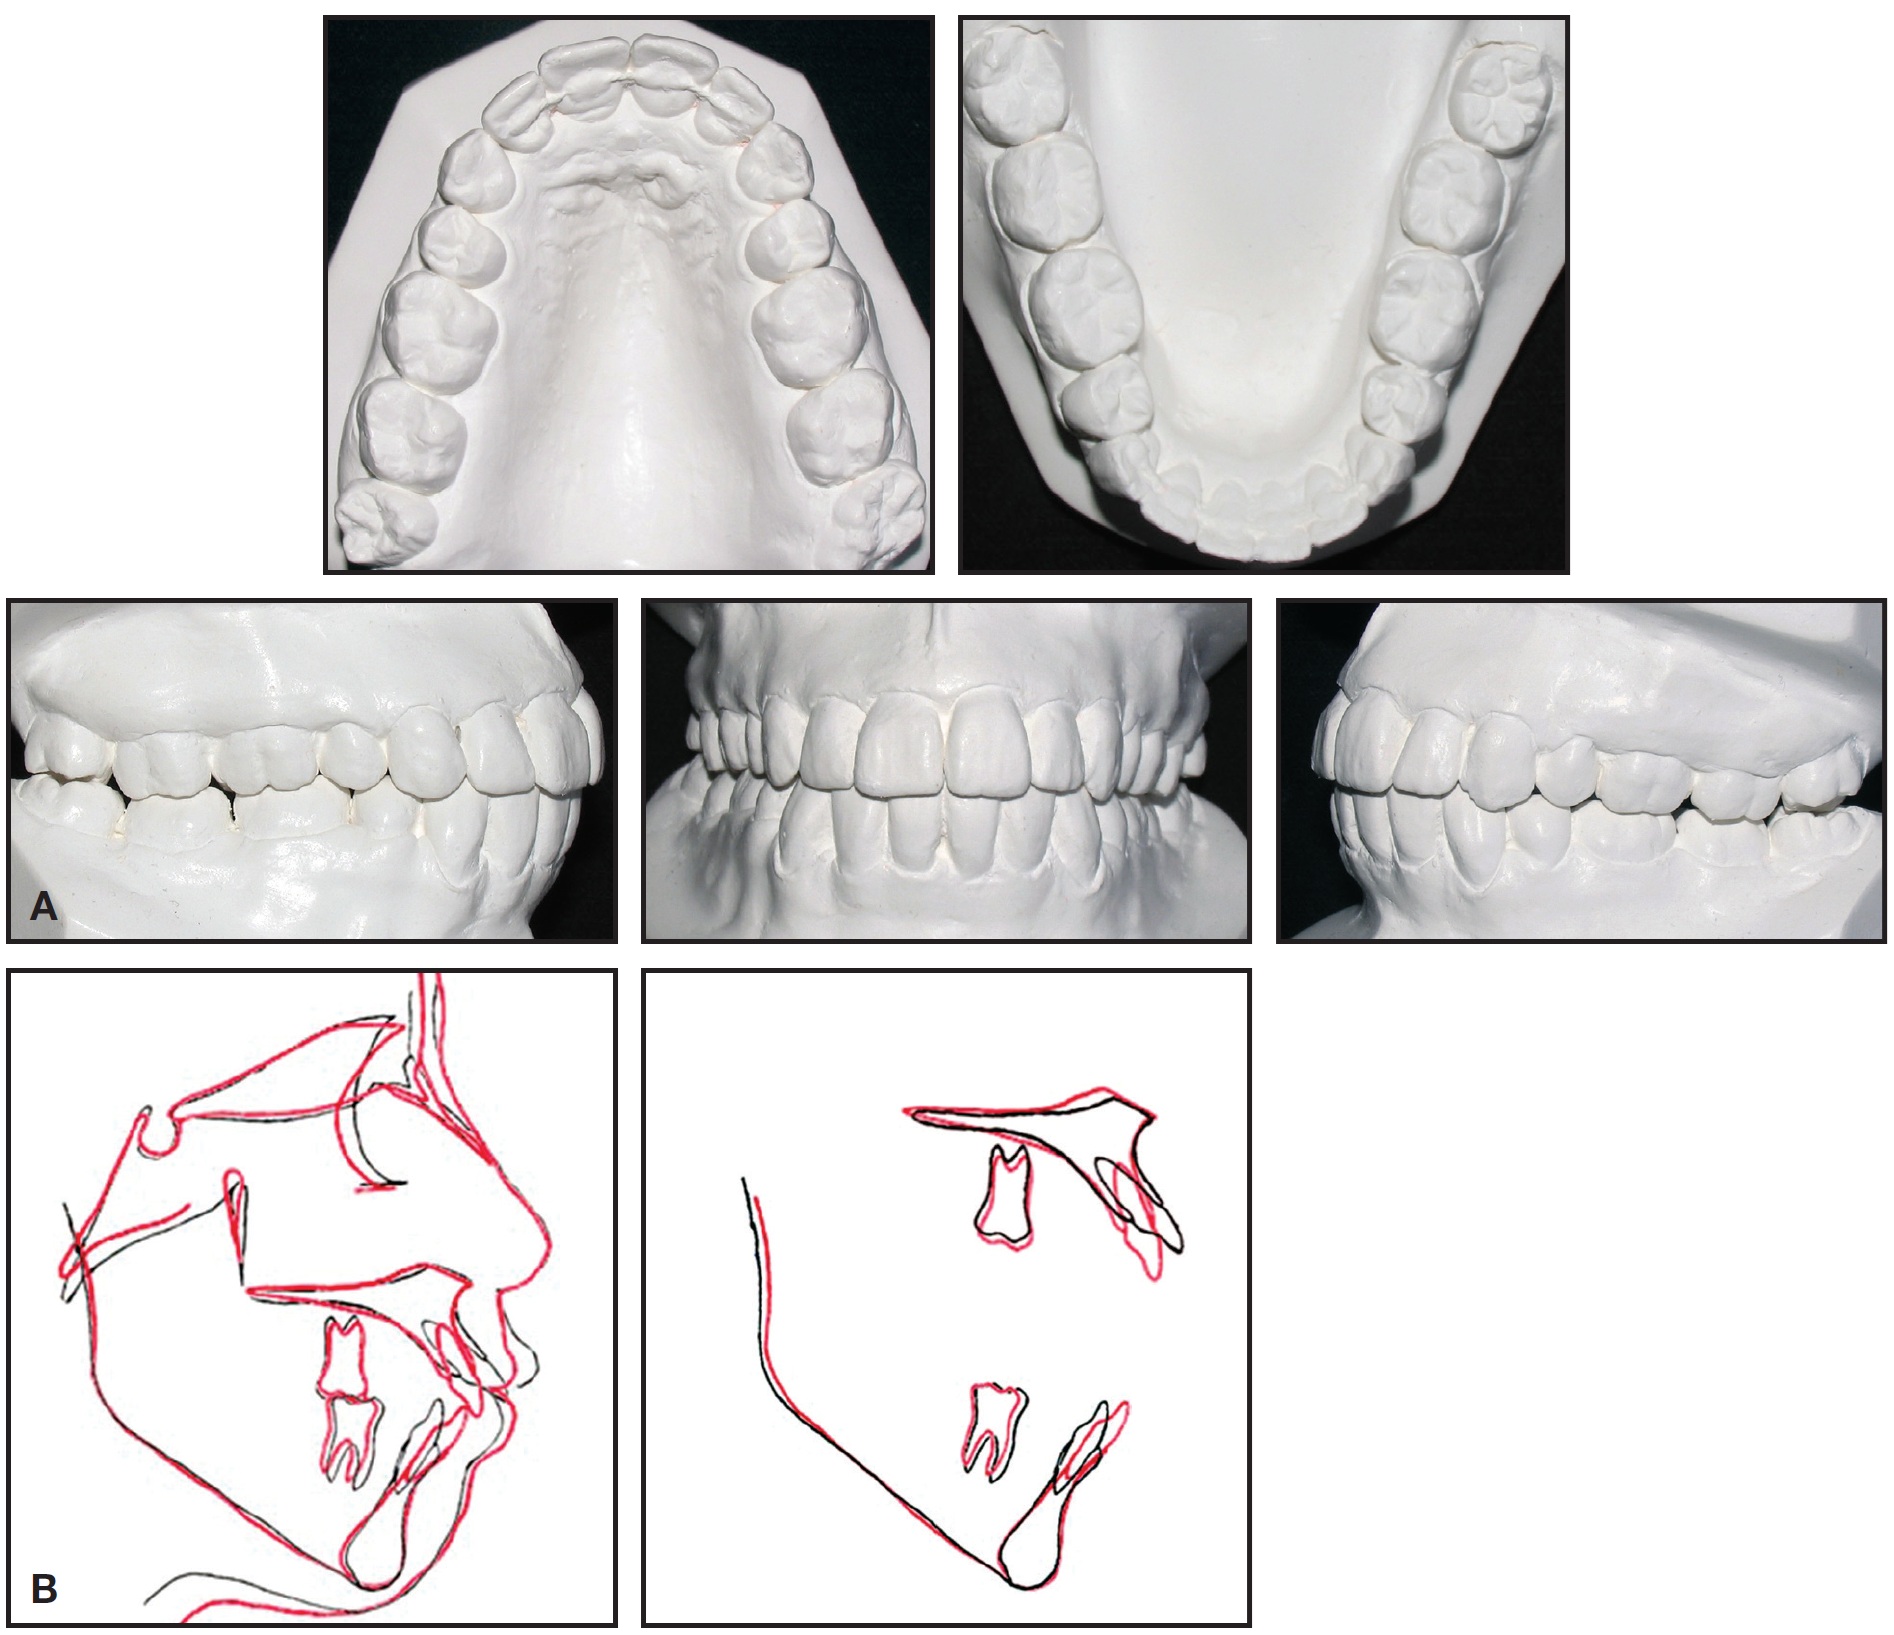

Fig. 1 27-year-old Class II female patient with severe lower crowding, 10mm anterior open bite, and severe hyperdivergence before treatment.

Fig. 1 (cont.) 27-year-old Class II female patient with severe lower crowding, 10mm anterior open bite, and severe hyperdivergence before treatment.

The intraoral photographs and dental casts revealed an anterior open bite of 10mm and an overjet of 15mm. In addition, two distinct occlusal planes were present in the upper arch. The lower arch had severe crowding, with the canines completely blocked out and the left first premolar and a supernumerary premolar blocked in. The upper dental midline was aligned with the facial midline, but the lower midline was deviated 2mm to the right. Sagittally, the molars were in a 2mm Class III relationship, the right canine was in a Class III relationship, and the left canine was in a full Class II relationship.

The patient was a mouth-breather and had a tongue thrust at rest. TMJ examination revealed clicking on both sides, with bayonet closure but no pain. Radiography showed a restoration at the level of the lower right first molar, as well as mesially inclined lower canines and premolars.

Cephalometric analysis indicated a skeletal Class II relationship with bimaxillary protrusion (Table 1).

The mandibular plane angle was steep, and the gonial angle was severely increased (MP-FH = 39 degrees). The upper incisors were extremely proclined; the lower incisors were retroclined. Treatment objectives were to correct the convex profile, reduce the lower facial height, widen the maxilla to ameliorate the V-shape archform, relieve the crowding, and achieve a Class I relationship with ideal overjet and overbite.